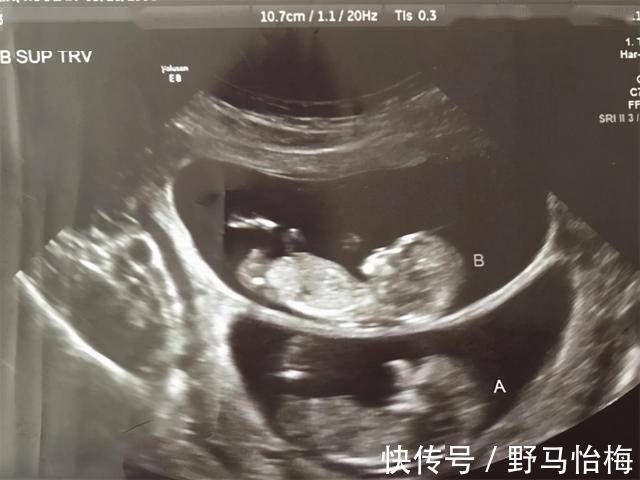

所以,孕妈们在产检的时候,最怕出现的就是有不一样的检查结果发生,有的孕妈在做B超的时候,总是会冷不丁地听到医生对着B超结果说上一句:XX偏大一周。于是,孕妈听完之后就会变得很紧张,偏大一周是怎么回事?是宝宝有什么问题吗?

其实,孕妇做B超时这种情况是经常发生的,而医生总说胎儿的检查结果显示要比实际天数多几天是为什么?

【 天数|孕妇做B超时,医生总是说胎儿比实际天数多几天是为什么?】相对于直接测量的结果, B超产检这种通过超声波的方式,隔着妈妈的肚皮、子宫和羊水的多重障碍来测量宝宝的发育情况,其中存在的误差就更多了。所以,在临床的检查上,B超只能算是一个接近实际的估算测量,并不等于宝宝的实际发育情况。

而且,B超对于胎儿发育情况的估算,主要参考的几个数值是: 双顶径、头围、腹围、股骨长、头臀径等 的各个肢体长度。然后再通过这些测量出来的数值来做发育情况的对比,从而间接的得出宝宝具体的发育情况,这就比较容易在对比之中存在着发育早晚的情况。